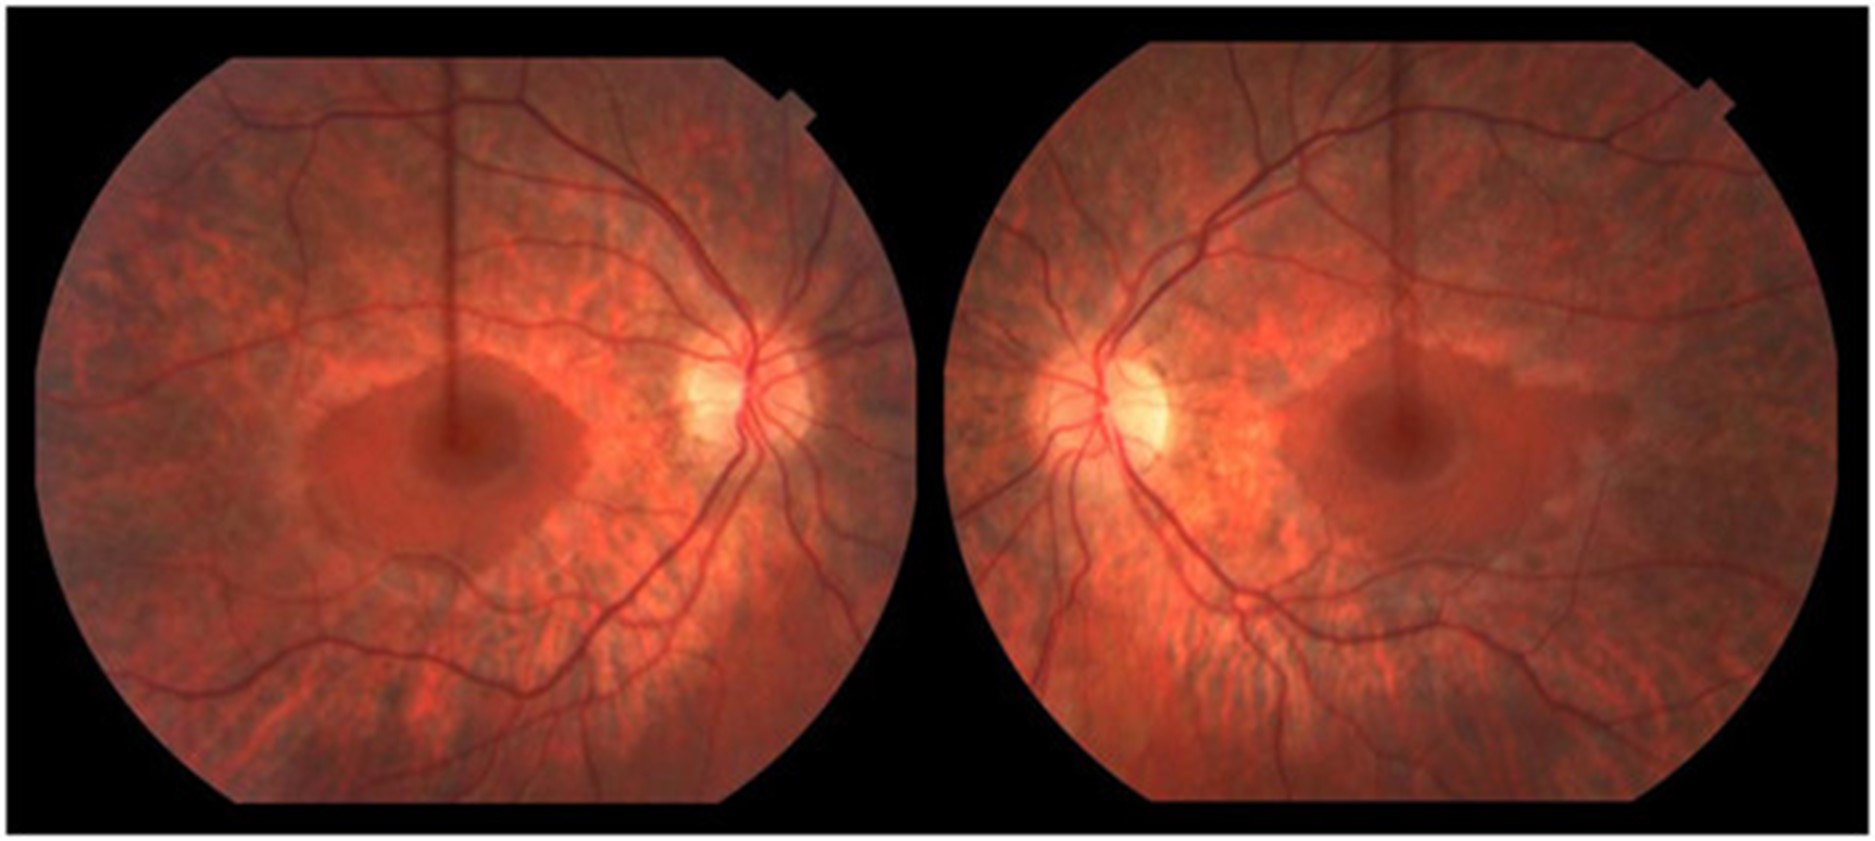

一名 16.5 岁的男孩在 3.5 岁时被诊断出语言表达迟缓和发音困难,这是由中度至重度感音神经性听力障碍引起的。他的语言发展在助听器的帮助下有效正常化。他早期的粗大和精细运动发育正常;他小时候会滑冰和打曲棍球。他在普通课堂环境中的学业成绩很好。11 岁时,他患上了隐匿的进行性步态共济失调。他被发现有双侧高弓足和轻度槌状趾足畸形、弥漫性反射消失和屈肌足底反应。注意到前间室肌肉非常轻度无力,因此使用了踝足矫形器。小纤维感官测试在库存分布中略有下降。振动觉和本体感觉保持完好。有明显的轻度不协调;快速手指运动缓慢,脚跟到胫骨测试受损。Romberg征阴性。神经传导研究(表1) 显示具有脱髓鞘特征的轻度感觉运动性多发性神经病(运动传导速度;20–25 m/sec;正常上肢≥50 m/sec,下肢≥40 m/sec)。感觉和运动神经振幅正常,但腓总神经 CMAP 振幅较低。随着时间的推移,他的高弓足恶化,他的神经传导研究显示进行性脱髓鞘(潜伏期延长增加)和长度依赖性轴突丧失(运动和感觉振幅进行性丧失)的证据。15.5 岁时的眼底镜检查显示广泛的周边视网膜萎缩伴中央黄斑(即严重的视杆细胞功能障碍伴视锥细胞相对保留)与色素性视网膜炎一致(图 1)。视力正常。视觉诱发电位正常。暗视杆状视网膜电图 (ERG) 显示轻度异常,表明周边视网膜的杆状细胞功能障碍。明视锥和 30 Hz 闪烁也异常,表明视锥功能障碍。在他 16.5 岁时的贼后一次临床随访中,他在家中可以进行短距离走动,但由于他严重的共济失调,长距离走动需要轮椅。他没有表现出生长或青春期延迟的迹象。他的身高在 10-25百分位之间,并且在 16 岁时,他被注意到具有与年龄相适应的青春期发育;Tanner IV 阴毛和 12-15 mL 睾丸体积。他的认知、语言和视觉都完好无损。他没有肾脏或肝脏受累的临床或生化证据。

这位 14 岁的弟弟在 2 岁时被确诊患有中度至重度感音神经性听力损失,需要助听器。他的早期神经发育正常。他仍然很活跃;贼后随访能够滑冰 3 公里和越野滑雪 1-1.5 小时。他不需要踝足矫形器或任何其他辅助设备。他的检查对非常轻度的高弓足和反射减退(二头肌 1+、肱桡肌 1+、三头肌 2+、髌骨 1+、踝反射 0)、屈肌底反应和轻度前间室无力(胫骨前肌 4+/5、腓骨肌)具有重要意义长肌 4+,拇长伸肌 4)。除了脚趾针刺感觉过敏外,感官测试正常。注意到轻微的脚踝紧绷。协调是正常的。神经传导研究(表1) 显示具有脱髓鞘特征的轻度感觉运动性多发性神经病。眼底检查显示广泛的周边视网膜萎缩,中央黄斑不受累。视力和 ERG 正常。他的认知完好无损,并且在常规课堂环境中取得了良好的学业成绩。尽管他的身高一直低于第 5个百分点,但他表现出正常的生长速度。在将近 14 岁的时候,他没有显示出阴毛初现的迹象,Tanner I 阴毛和 5 mL 睾丸体积。他的实际年龄为 13 岁 8 个月,骨龄为 11 岁,符合体质性生长和青春期延迟。他没有显示肾脏或肝脏受累的证据。